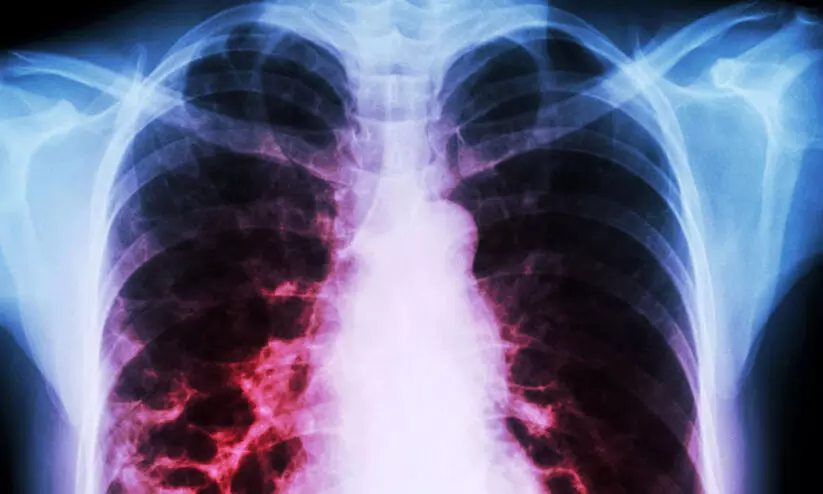

ശ്വാസകോശ രോഗികളുടെ എണ്ണത്തില് ഇന്ത്യ രണ്ടാമത്

text_fieldsകൊച്ചി: ശ്വാസകോശ രോഗികളുടെ എണ്ണത്തില് ഇന്ത്യ ആഗോള തലത്തില് ചൈനക്ക് പിന്നിൽ രണ്ടാംസ്ഥാനത്തെന്ന് ആഗോള രോഗസാധ്യതാ പഠനം. ഇന്ത്യയില് 55 ദശലക്ഷത്തിലധികം വിട്ടുമാറാത്ത ശ്വാസകോശ (ക്രോണിക് ഒബ്സ്ട്രക്ടിവ് പള്മണറി ഡിസീസ്) രോഗികളുണ്ടെന്ന് ആലപ്പുഴ ജില്ല ആശുപത്രിയിലെ ഡോ. വേണുഗോപാല് ചൂണ്ടിക്കാട്ടി. പുകവലി, വ്യവസായങ്ങളില്നിന്നുള്ള പുക, ചൂള തുടങ്ങിയവയുമായുള്ള ദീര്ഘകാല നിരന്തര സമ്പര്ക്കം എന്നിവ ശ്വാസകോശ രോഗത്തിന് വഴിയൊരുക്കുമെന്നും അദ്ദേഹം പറഞ്ഞു.

ശ്വാസകോശ ആഘാതമേറ്റ ഒരു രോഗി എത്തുമ്പോഴേക്കും രോഗിയുടെ ശ്വാസകോശം ഗുരുതരമായി കുഴപ്പത്തിലായിട്ടുണ്ടാകും. നേരത്തേ കണ്ടെത്തിയാലേ നല്ല പരിപാലനം സാധ്യമാക്കാനും രോഗിയുടെ ജീവിത നിലവാരം മെച്ചപ്പെടുത്താനും കഴിയൂ. ബി.പി, ഷുഗര് എന്നിവ പോലെതന്നെ ശ്വാസകോശ പരിശോധനയും പൊതുജനത്തിെൻറ മനസ്സിലുണ്ടാകണമെന്നും അദ്ദേഹം പറഞ്ഞു.

നേരത്തേയുള്ള രോഗനിര്ണയം, ശരിയായ ചികിത്സ, ചികിത്സ പാലിക്കല്, സ്ഥിതി കൃത്യമായി കണക്കാക്കല് തുടങ്ങിയവയെല്ലാം ശ്വാസകോശ ആഘാതം തടയുന്നതില് നിര്ണായക നടപടികളാണെന്ന് കോഴിക്കോട് മൈത്ര ആശുപത്രിയിലെ ഡോ.കെ. മധു പറഞ്ഞു.